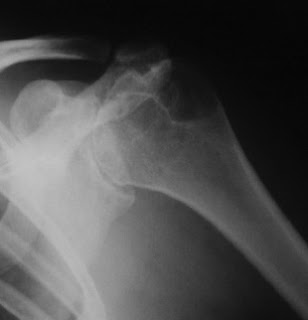

The tightness of the joint also makes anatomic positioning of a resurfacing implant difficult as shown below.